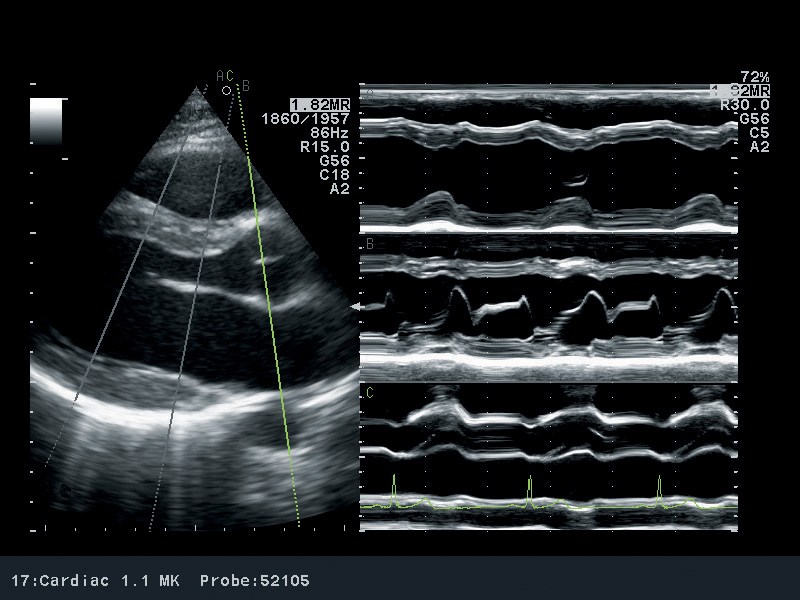

M-режим (M – motion) – режим одномерного сканирования с получением развертки в реальном масштабе времени, который применяется для регистрации пространственного положения исследуемых объектов во времени (отслеживания движения исследуемых структур).

М-режим, одномерный

Такой режим работы УЗИ обычно используют для проведения кардиологической диагностики. Он отображает на экране ткани сердечной мышцы в движении. Это даёт возможность оценить их упругость и эластичность.

М-режим был предпочтительным методом визуализации на заре УЗИ. М-режим определяется как отображение во времени движения ультразвуковой волны вдоль выбранной ультразвуковой линии. Он обеспечивает мономерное изображение сердца.

Все отражатели вдоль этой линии отображаются по оси времени. Преимущество М-режима заключается в очень высокой частоте дискретизации, что обеспечивает высокое временное разрешение, позволяющее записывать, отображать и измерять даже очень быстрые движения. Недостатком является то, что ультразвуковая линия закреплена на кончике ультразвукового сектора. Поэтому может быть сложно выровнять М-режим перпендикулярно отображаемым структурам (например, перегородке), что приведет к ложным измерениям.

Анатомический М-режим обходит это ограничение, реконструируя М-режим из 2D-изображения (постобработка). Анатомический М-режим позволяет свободно позиционировать линию курсора. Однако временное разрешение значительно меньше, чем у обычного М-режима.

М-режим можно комбинировать с другими методами визуализации, такими как цветовой допплер или тканевой допплер.

М-режим или режим движения — это не изображение сердца, а скорее схема, показывающая, сердечные структуры перемещаются во время сердечного цикла.

Запись в М-режиме обычно выполняется в парастернальных проекциях. В парастернальной проекции по длинной оси курсор М-режима должен проходить через малую ось аорты и левого предсердия, кончики створок митрального клапана и малую ось левого желудочка чуть выше папиллярной мышцы. В парастернальной проекции по короткой оси М-режим может быть сделан из передней и задней створок митрального клапана, а через малую ось левого желудочка чуть ниже митрального аппарата.

М-режим отображает время по горизонтальной оси и глубину по вертикальной оси для отображения движения сердечных клапанов и движения стенки (рис. 1).